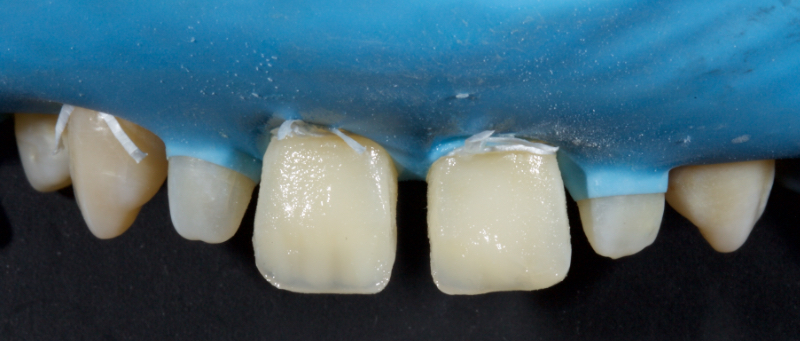

The anterior teeth had lost around 25% of the coronal structure, and dentin was exposed (Figs. 1–3). The patient requested a minimally invasive solution.

After deprogramming with a splint and occlusal equilibration, the anterior teeth were restored with direct composite resin using a minimal prep approach (Figs. 4 and 5). The occlusal scheme was idealized (Fig. 6).